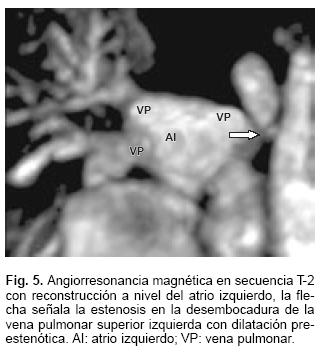

La radiografía de tórax mostró cardiomegalia grado III y flujo pulmonar aumentado. En el ecocardiograma (Fig. 1) se observó que la rama derecha de la arteria pulmonar (RDAP) nacía de la aorta ascendente. Había marcada hipertensión arterial pulmonar. Tenía mala función ventricular con fracción de eyección de 33%. El estudio hemodinámico (Figs. 2 y 3) demostró que la presión sistólica de la rama izquierda de arteria pulmonar era suprasistémica de 80 mm Hg y en la rama derecha era de 60 mm Hg, igual a la sistémica; se observó gran retardo del vaciamiento de la vena pulmonar izquierda; había un conducto arterioso permeable. La angiorresonancia magnética (Figs. 4 y 5) corroboró los diagnósticos y mediante la reconstrucción permitió ver una estenosis de la vena pulmonar superior izquierda. Por la edad de la paciente y la presencia de la obstrucción venosa pulmonar fija, se consideró candidata a cirugía.